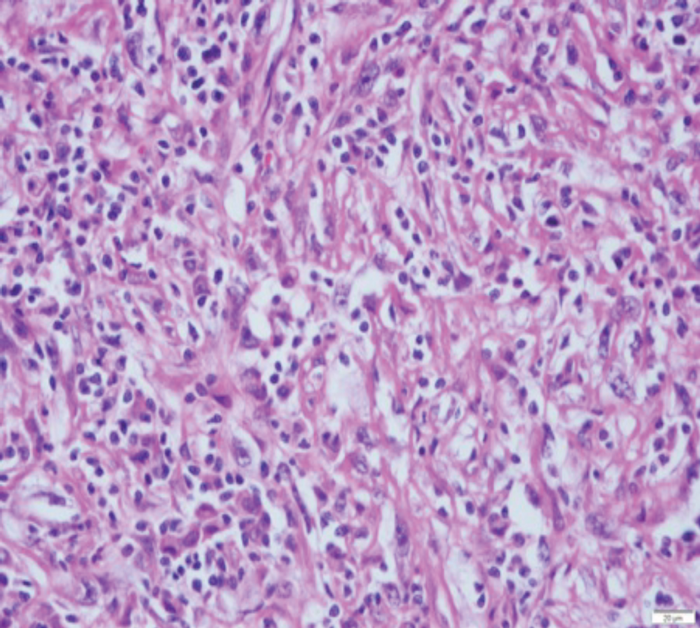

Figure 2: (A) sRCC tumour. (B) sRCC metastases to lymph node.

sRCC macroscopically, has a solid white appearance [Figure 1]. Microscopically, it contains spindle-like cells, cellular atypia and high cellularity which are features found in sarcomas [Figure 2]. They do not contain epithelial components and they can be uniform or heterogeneous. The majority will contain some carcinoma elements, while 90% will have tumour necrosis and 30% will have lymphovascular invasion. More than 80% of sRCC are found in clear cell carcinoma [10]. sRCC tends to be associated with high grade tumours however, more than 30% can also be found in low grade tumours [11]. Due to its aggressive nature and poor prognosis it is often looked at as independent prognostic factor when managing RCC.